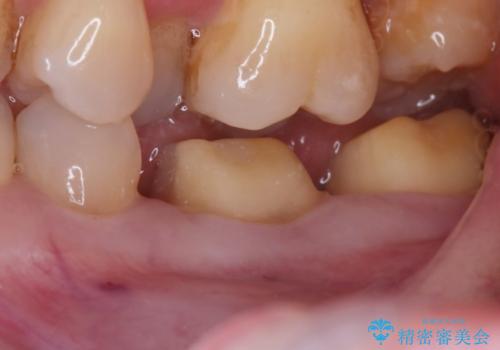

- ご友人との会話中などに、下の歯に入れてあるメタルインレーが見えてしまうのが気になり、やり変えを希望された患者様です。審美性、清掃性に優れたセラミックでの治療を希望されたため、セラミックインレー、クラウンで治療いたしました。

口を開けた際の見た目が向上し、非常に満足いただけました